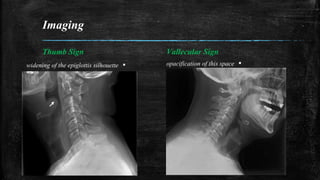

plain film radiography can be used for screening purposes.

Findings on plain film suggestive of Epiglottitis include

the “Thumb Sign” (widening of the epiglottis silhouette)

and the “Vallecular Sign” (opacification of this space).

Imaging

Thumb Sign

▪widening of the epiglottis silhouette

Vallecular Sign

▪opacification of this space